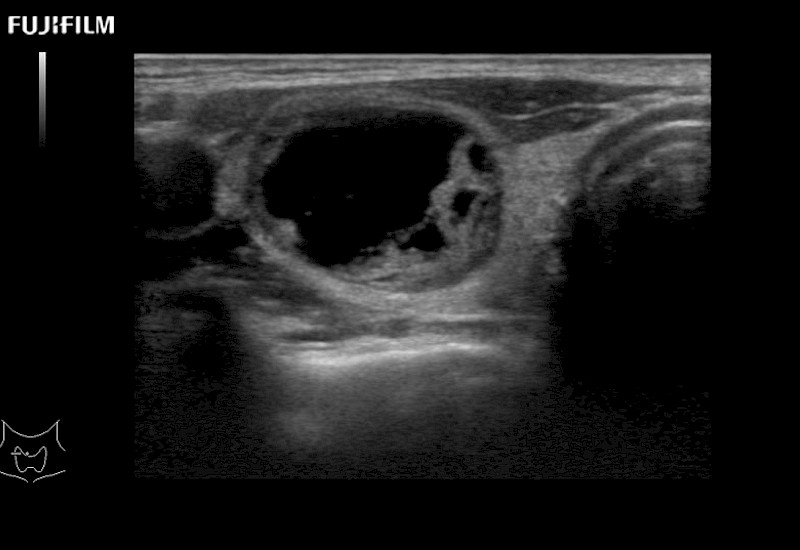

Extraordinary high-resolution digital imaging

- Ideal for liver and kidney scanning

- Ideal for liver and kidney scanning

- Ideal for liver and kidney scanning